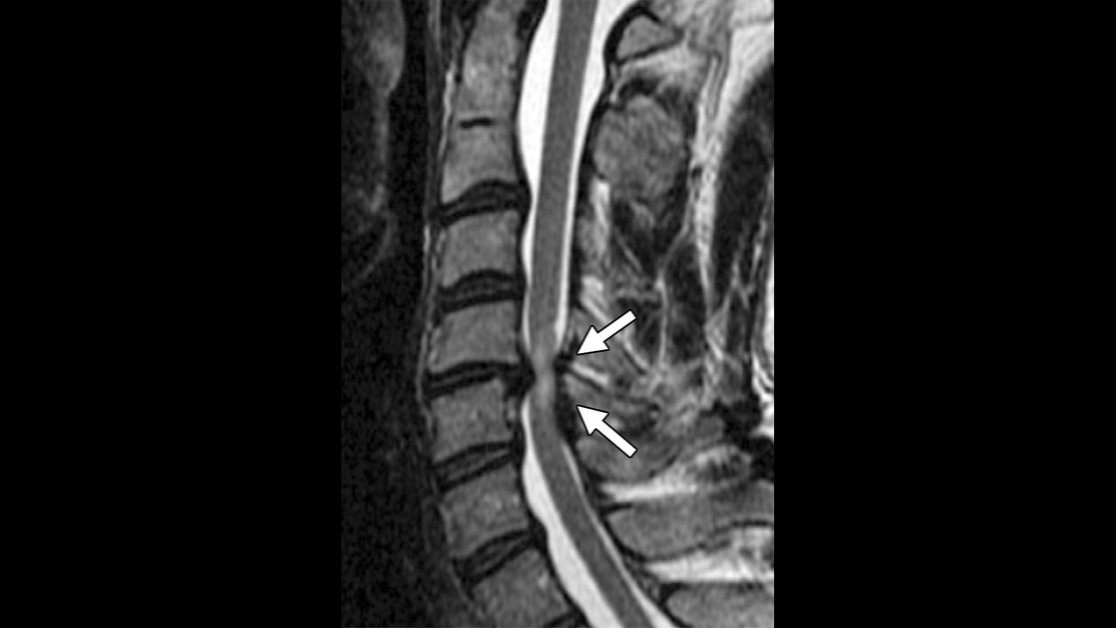

When evaluating suspected nontraumatic spinal cord injury, consider a compartmental spinal

#MRI approach that helps localize the abnormality to an epidural, intradural extramedullary, or intramedullary space. https://bit.ly/2VncXX0@laur_olga@KhuranaBharti@BWHRadEdupic.twitter.com/26s5lCinWH